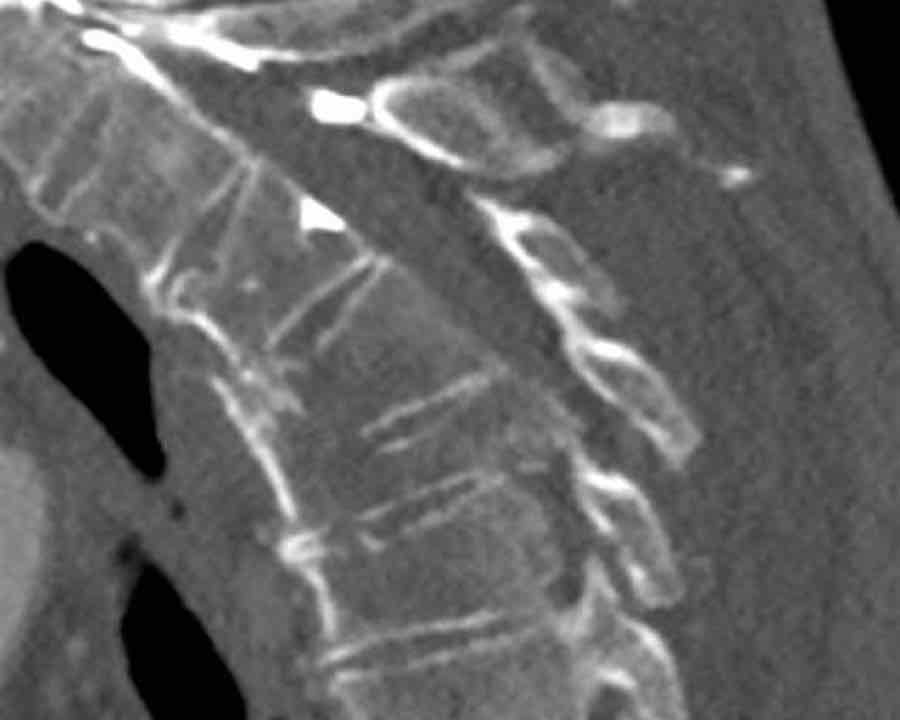

Scroll through the images.

What are the findings?

What is the highest AO-type of injury?

Findings

- Vertical fracture of the posterior border of the vertebral body. It looks a bit odd.

- Again we first have to look for the presence of a type C injury.

- Notice that there is a subtle posterior dislocation of the proximal levels. So this has to be C injury.

Conclusion

Injury type C + A3